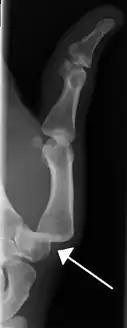

Dislocation of the left index finger

Radiograph of right fifth phalanx bone dislocation

Radiograph of left index finger dislocation